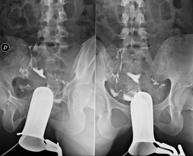

La urografia intravenosa (UIV) consisteix en l'obtenció d'imatges radiològiques seriades del ronyó, vies urinàries i bufeta. Aquest estudi requereix sempre l'ús d'un contrast iodat. - Cistografía (CUMS)

La cistouerotrografia miccional seriada consisteix en l'obtenció d'imatges radiològiques per valorar l'anatomia i la funció de la uretra i la bufeta amb l'administració de contrast iodat a través d'una sonda vesical. - Uretrocistografia (Uretro-Cums)

La uretrocistrografia retrògrada i miccional consisteix en l'obtenció d'imatges radiològiques per valorar l'anatomia i la funció de la bufeta i de la uretra. S'aplica material de contrast a través d'una petita sonda que es troba a la uretra i s'obtenen imatges durant l'ompliment i el buidatge de la bufeta. - Pielografia ascendent per catèter

Prova diagnòstica que consisteix en la visualització de l'urèter i de la pelvis renal mitjançant l'ús de raigs X en aquells pacients portadors d'un catèter mitjançant la injecció d'un contrast iodat a través del catèter.

- Pielografia per nefrostomia

Prova diagnòstica que consisteix en la visualització del tracte urinari mitjançant l'ús de raigs X en aquells pacients portadors d'un catèter de nefrostomia mitjançant la injecció d'un contrast iodat a través del catèter.

- Cystography

Serial voiding cystourethrography involves radiological imaging to assess the anatomy and function of the urethra and bladder with the administration of iodinated contrast through a bladder catheter.